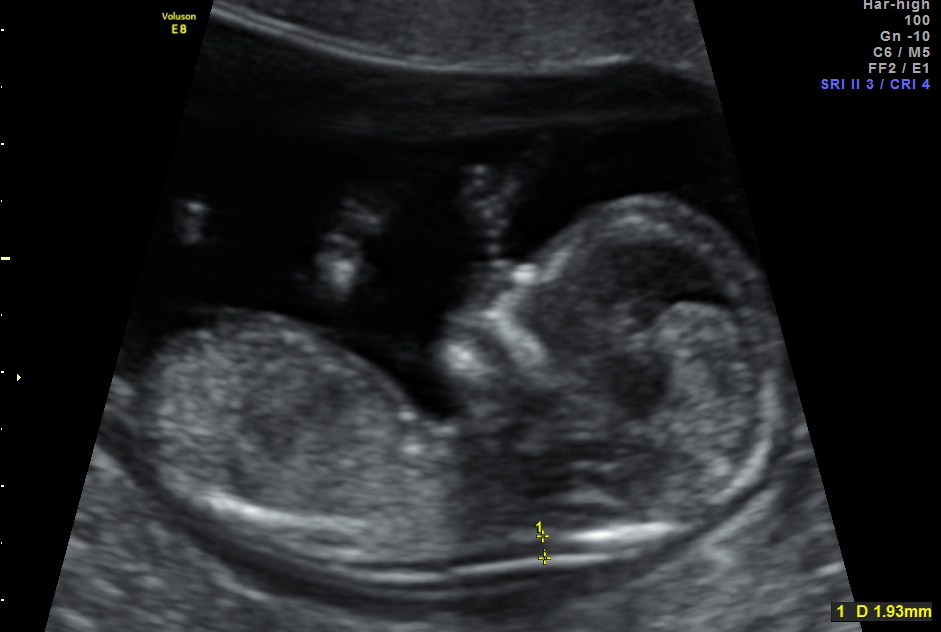

Fetal ense kalınlığı (NT) (Nukhal geçirgenlik=Nuchal translucency) ultrasonografide bebeğin boynunun arka kısmında koyu renkli olarak görünen kısmın kalınlığını ifade eder. 11 hafta 1 gün ile 13 hafta 6 gün arasındaki gebelere uygulanır.

Ense kalınlığının 3 milimetreden fazla olması artmış fetal ense kalınlığı olarak kabul edilmektedir.

NT kalınlığı ne kadar artmışsa fetusta bir anomali olma riski de buna paralel olarak o kadar artar. NT'nin her gebelik haftasına göre normal değerleri belirlenmiştir. Bu değerlere göre yüzde kaçlık artış (persantil) olduğuna göre risk belirlenir. NT kalınlığı gebelik haftasına göre %90-95 persantil arasında olan fetusların %90'dan fazla olasılıkla anomalisiz olma şansı vardır. NT %99 persantil üzerinde olan olgularda anomali riski çok fazladır. Bu olgularda CVS ile fetusta kromozomal anomali olup olmadığı değerlendirilebilir ve detaylı ultrason incelemesi ile fetustaki olası anomaliler taranır. Bu NT'si çok artmış olarak bulunan fetusların 14-16 hafta arası tekrar değerlendirilmesi önemlidir, bu haftalarda ense ödemi geriler ve normal sınırlara inerse bu iyi bir göstergedir ve bebekte anomali olma riskinin düşük olduğunu gösterir. Eğer 14-16 hafta arası yapılan tekrar değerlendirilmede ense kalınlığı azalmamışsa bu fetusta genetik bir anomali yada enfeksiyon olma olasılığı yüksektir.

Fetal ense kalınlığı (NT) (Nukhal geçirgenlik=Nuchal translucency) ultrasonografide bebeğin boynunun arka kısmında koyu renkli olarak görünen kısmın kalınlığını ifade eder. 11 hafta 1 gün ile 13 hafta 6 gün arasındaki gebelere uygulanır.

Ense kalınlığının 3 milimetreden fazla olması artmış fetal ense kalınlığı olarak kabul edilmektedir.

NT kalınlığı ne kadar artmışsa fetusta bir anomali olma riski de buna paralel olarak o kadar artar. NT'nin her gebelik haftasına göre normal değerleri belirlenmiştir. Bu değerlere göre yüzde kaçlık artış (persantil) olduğuna göre risk belirlenir. NT kalınlığı gebelik haftasına göre %90-95 persantil arasında olan fetusların %90'dan fazla olasılıkla anomalisiz olma şansı vardır. NT %99 persantil üzerinde olan olgularda anomali riski çok fazladır. Bu olgularda CVS ile fetusta kromozomal anomali olup olmadığı değerlendirilebilir ve detaylı ultrason incelemesi ile fetustaki olası anomaliler taranır. Bu NT'si çok artmış olarak bulunan fetusların 14-16 hafta arası tekrar değerlendirilmesi önemlidir, bu haftalarda ense ödemi geriler ve normal sınırlara inerse bu iyi bir göstergedir ve bebekte anomali olma riskinin düşük olduğunu gösterir. Eğer 14-16 hafta arası yapılan tekrar değerlendirilmede ense kalınlığı azalmamışsa bu fetusta genetik bir anomali yada enfeksiyon olma olasılığı yüksektir.